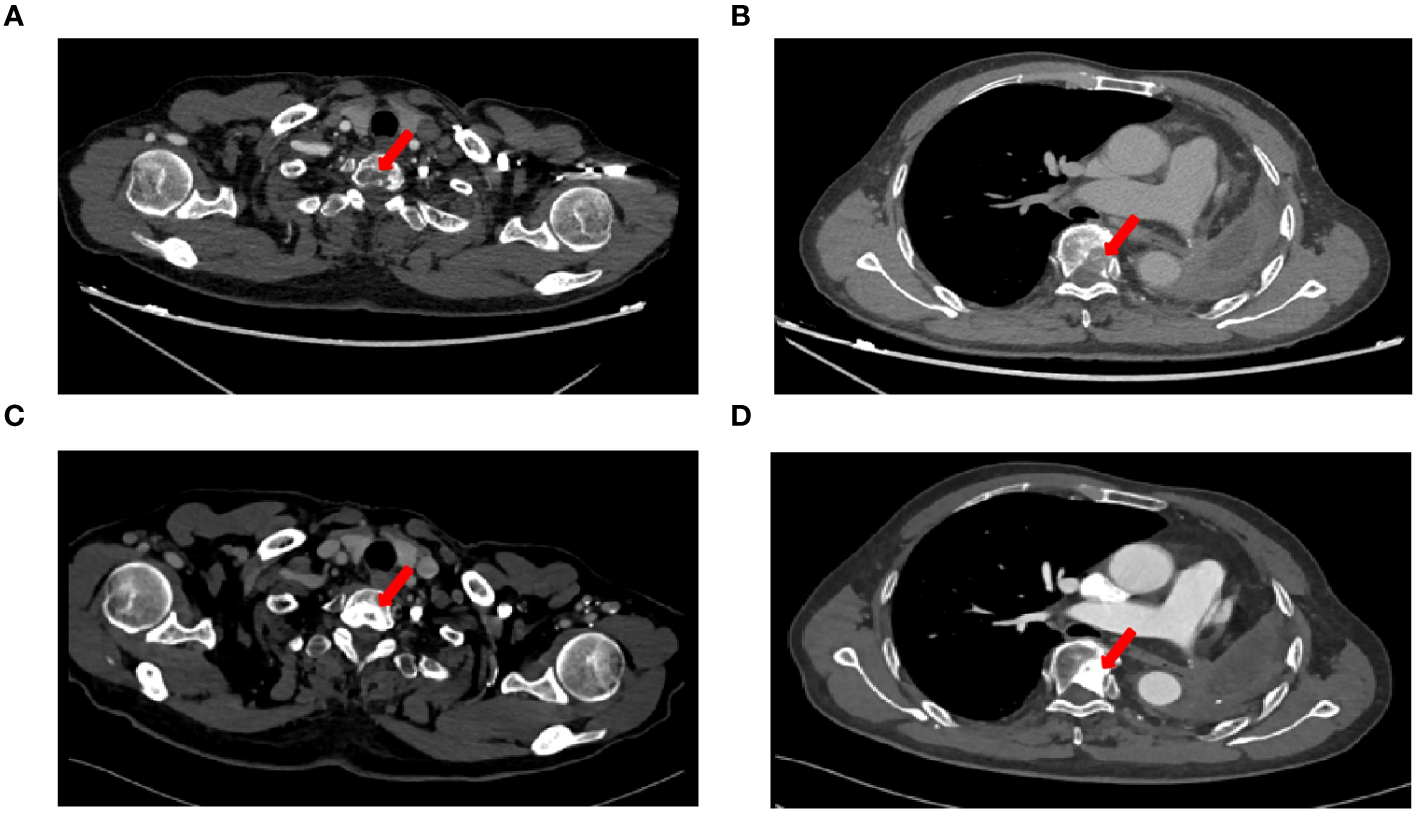

A 71-year-old male, with a smoking history of over 40 years, was admitted to The First Affiliated Hospital of Gannan Medical University (Ganzhou, China) on October 16, 2016, with a persistent cough lasting for 9 months and hemoptysis for 1 week. CT revealed a mass in the upper lobe of the left lung. On October 20, 2016, the patient underwent a total resection of the left lung and systemic lymph node dissection under general anesthesia. Postoperative pathology revealed lung adenocarcinoma, and one-third of the hilar lymph node metastases was positive. Immunohistochemistry revealed TTF-1 (+), CK7 (+), Napsin A (+), and Ki-67 expression (approximately 20%). The postoperative diagnosis was stage IIA (pT1bN1M0), according to the 7th edition of the TNM classification for lung cancer. Genetic testing using ARMS revealed the EGFR21 L858R mutation. After surgery, the patient received four cycles of adjuvant chemotherapy with docetaxel and cisplatin. On July 23, 2019, the patient presented with headache and pain in the neck and chest. MRI and CT scans indicated metastases in the T1 and T6 vertebrae (Figures 1A, B). Subsequently, the patient underwent radiotherapy for vertebral metastases at a dose of 30 Gy/10 fx along with molecular-targeted therapy using gefitinib (Iressa, 250 mg/day). During regular follow-up examinations, the disease remained stable, with osteogenic changes observed in the thoracic vertebral metastases (Figures 1C, D). In May 2021, CEA levels increased from 9.7 ng/ml to 214 ng/ml, accompanied by the onset of a grade 3 rash following the oral administration of gefitinib. Consequently, target therapy was switched to osimertinib at 80 mg/day. After one month, the CEA decreased to 161.5 ng/ml and the rash improved to grade 1. In September 2021, the patient presented with dizziness, headache, nausea, vomiting, and weakness in both lower extremities. Magnetic resonance imaging (MRI) revealed significant thickening and pronounced enhancement of the meninges in the cerebellum (Figures 2A–C). A lumbar puncture confirmed the presence of cancer cells in the cerebral effusion, suggesting meningeal metastasis (Figure 3A). Second-generation CSF sequencing (OncoDrug-Seq sequencing platform: Illumina NextSeq500vaSeq) identified an EGFR21 L858R mutation with an abundance of 38% in combination with TP53 and FGFR3 mutations. Subsequently, the patient received a double dose of osimertinib (160 mg/day) for 2 months; however, there was no significant improvement in the dizziness or headache. Starting in November 25, 2021, the patient received an intrathecal injection of 30 mg pemetrexed, administered 1-2 times per week, 2-3 times per course and repeated once every 2-3 months. Additionally, the patient was prescribed one centrum tablet daily and continued targeted therapy with osimertinib (160 mg/day). Following one course of intrathecal chemotherapy, the symptoms of dizziness and headache were alleviated, and after three courses of intrathecal chemotherapy, the thickening and pronounced enhancement of the meninges in the cerebellum disappeared (Figures 2D–F), and CSF cytology was negative (Figure 3B). The patient underwent a total of 12 intrathecal injections of pemetrexed from November 2021 to November 2022. The patient has a good quality of life, and no disease progression is observed. Adverse drug reactions include grade 1 rash, grade 1 leukopenia, grade 1 thrombocytopenia, and fatigue. Considering the absence of evident neurological symptoms and negative CSF cytology, intrathecal pemetrexed chemotherapy is discontinued, and only 160 mg osimertinib targeted therapy is currently being utilized. The patient exhibites mild weakness of the lower limbs as the main clinical symptom with no apparent adverse drug reactions. Since the diagnosis of LM, the patient has survived for 28 months (Figure 4).

Figure 1

CT imaging changes before and after treatment. (A) Chest CT images on 23 July, 2019 showed T1 vertebral metastasis, (B) Chest CT images on 23 July, 2019 showed T6 vertebral metastasis, (C) Chest CT images showed osteogenic changes of T1 vertebral metastasis after radiotherapy, (D) Chest CT images showed osteogenic changes of T6 vertebral metastasis after radiotherapy.